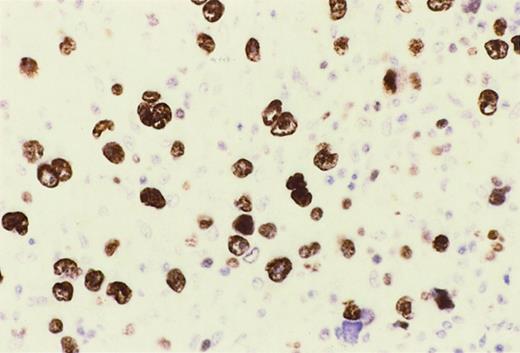

Reed-Sternberg cells of HIV-HL express MUM1.

In a lymph node involved by lymphocyte depletion HIV-HL (case 16, Table4), MUM1 is expressed by a large number of tumor cells corresponding to RS cells and their variants. The staining is nuclear and intense. Immunoperoxidase, hematoxylin counterstain. Original magnification, × 250.